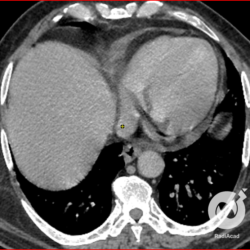

Lesões intersticiais reticulares difusas, aumento do volume cardíaco e inversão da circulação pulmonar (Rx)/ opacidades em vidro fosco e estruturas venosas calibrosas (TC).

Lesões intersticiais reticulares difusas, cardiomegalia, derrame pleural á direita (Rx)/Opacidades em vidro fosco, cardiomegalia e aumento do calibre das estruturas venosas.